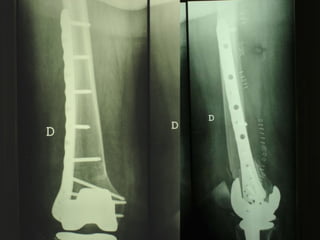

Dal Gennaio 2000 al Dicembre 2005 27 placche LISS di femore

Osso porotico Stabilità con viti autobloccate

INDICAZIONI COMUNI Fratture sovracondiloidee Fratture intercondiliodee Fratture diafisarie distali PARTICOLARI Fratture con grave osteoporosi Fratture periprotesiche

VANTAGGI CHIRURGIA MININVASIVA Mini Open Inserimento della placca sottocutaneo per scivolamento Viti percutanee Preservazione dei tessuti molli Ridotto danno vascolare Rapida ripresa funzionale

Conclusioni Riduzione  anatomica Minimo trauma chirurgico Corretto equilibrio fra elasticità e stabilità Precoce mobilizzazione